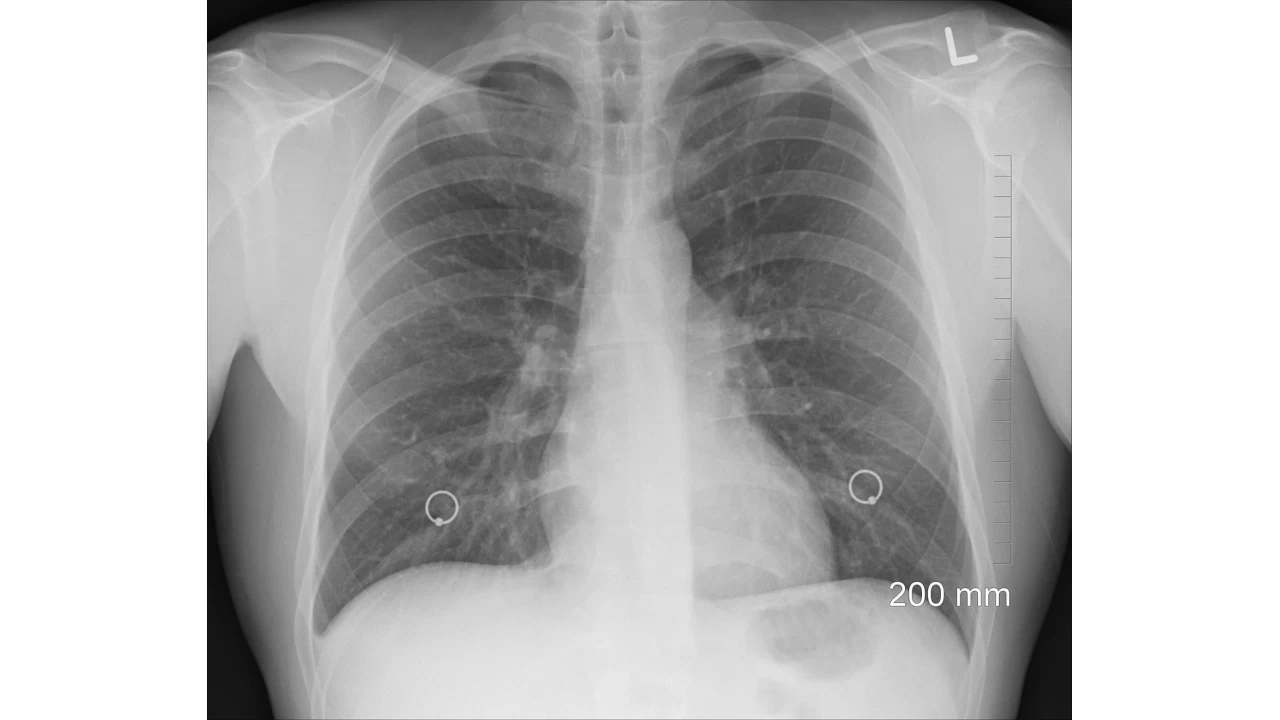

Akciğer sönmesi, tıbbi literatürde atelektazi veya bazı durumlarda pnömotoraks olarak adlandırılan, akciğer dokusunun bir kısmının veya tamamının normal şekilde genişleyememesi durumudur. Bu durum, akciğerin hava ile dolmasını engeller ve dolayısıyla oksijen alışverişini azaltır. Sonuç olarak, vücut yeterli oksijeni alamaz ve nefes darlığı, öksürük veya göğüs ağrısı gibi belirtiler ortaya çıkabilir.